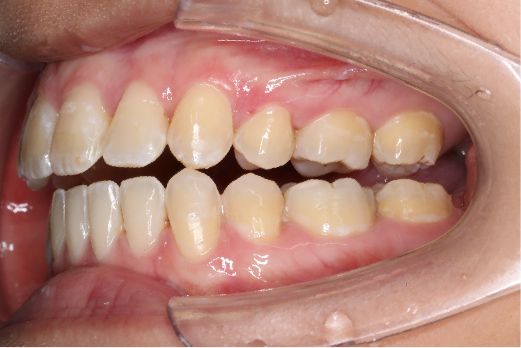

• 磨牙,尖牙I类关系,中线齐

• 上下牙列中度拥挤

• 上下前牙唇倾

IntraoralExamination(2016-08.31,Wu)

2018.11.14  术后磨牙尖牙I类关系,中线齐,覆合,覆盖正常